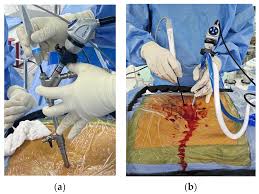

Endoscopic Spine Surgery is a technique wherein Surgery is done through less than 1cm incision using a special instrument called endoscope .

Minimally Invasive Spine Surgery (MISS) or Key Hole Spine Surgery is a technique wherein Surgery is done through tubular system under microscopic guidance.